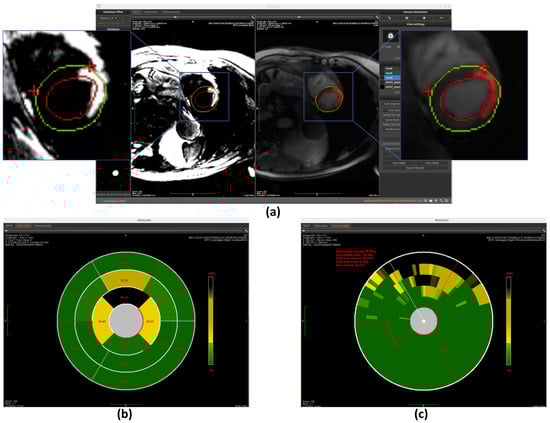

The region growing algorithm provides a semi-automated approach for myocardial scar detection through iterative pixel aggregation. Beginning from a user-defined seed point, in our case, it is the gravity center, and the method expands the region by progressively incorporating adjacent pixels that meet predefined similarity criteria. The algorithm operates under spatial confinement within the epicardial boundary and intensity homogeneity relative to the evolving region mean as constraints. During each iteration, the 4-connected neighborhood of the current region is evaluated, with qualifying pixels added to a dynamically managed candidate list. The pixel exhibiting minimal intensity deviation from the current region mean is incorporated into the growing scar region, followed by immediate recalculation of the updated region statistics. This adaptive process continues until either the maximum allowed intensity deviation is exceeded or the entire myocardial area has been evaluated. The final binary output delineates the detected scar region while maintaining topological consistency with myocardial anatomy. (The detection result is shown in Figure 11a) This method complements fully automated detection approaches by allowing refinement of scar boundaries.

Once the segments are accurately divided, the model calculates the scar area as a percentage of the total area within each segment. This is done by measuring the number of pixels corresponding to the scar in each segment and dividing it by the total number of pixels in that segment. These percentage values are then mapped to the corresponding positions on the bullseye plot, visually representing the spatial distribution of myocardial scars, as shown in Figure 7b, Figure 10b, and Figure 11b.

Once the segmentation is established, the model quantifies transmurality by assessing the proportion of scar tissue along each chord. For each chord, the ratio of scar thickness to the total myocardial wall thickness along the corresponding radial path is computed, reflecting the extent of myocardial wall affected. These transmurality values are then visualized in the bullseye plot, offering a high-resolution visualization of scar depth throughout the myocardium, as shown in Figure 7c, Figure 10c, and Figure 11c.

Figure 11. Overview of scar detection using the region growing method. (a) Detected myocardial scar visualized on the BR-LGE image—highlighted as the red region between the left ventricular endocardium (red circle) and the epicardium (green circle), alongside comparison with the corresponding BL-LGE image. (b) Infarct size visualization using an AHA 16-segment bullseye model. (c) Transmurality evaluation presented with a bullseye plot composed of 100 equally spaced chords.